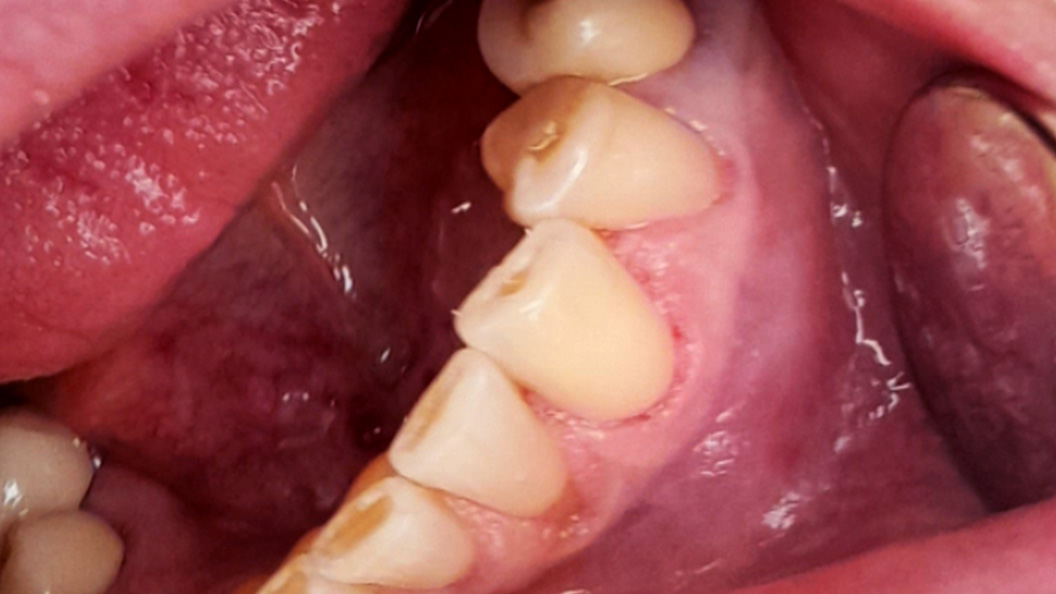

До и после лечения

В стоматологию обратилась пациентка с жалобами на быстро проходящую боль от холодного в районе клыка нижней челюсти. Врач провёл осмотр, а также реакцию зуба на холодный воздух и зондирование. В результате выявлена кариозная полость. Поставлен диагноз — средний кариес зуба 3.3 (вестибулярно). Проведено лечение с использованием композита светового отверждения Эстелайт.

В ходе лечения врач провёл следующие манипуляции:

- инфильтрационная анестезия;

- ретракция десны нитью;

- механическая и медикаментозная обработка кариозной полости;

- наложение изолирующей прокладки;

- постановка пломбы из материала Эстелайт.